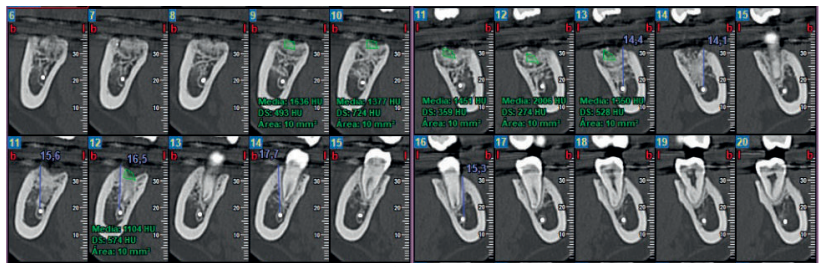

A los 6 meses se realizó una tomografía computarizada de haz cónico (Figura 11), para calcular la densidad ósea en el lado control (1372,33 Unidades Hounsfield) respecto al lado de estudio (1602,33 Unidades Hounsfield). Además, se comparó la altura a la cresta ósea en el lado control (disminución de 2,1 mm de altura ósea) respecto al lado de estudio (disminución de 0,9 mm de altura ósea).